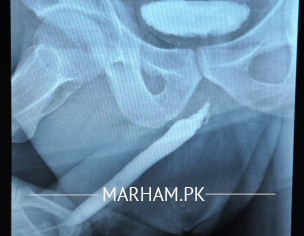

1 time Uretheroplast 1 time Optical and 1 Time again uretheroplasty plus Graff Karwaa Chukaa Huu. But again Wohi Problem Face karne ko Mil rhi he Urine me takleef Our RUG ka Test karwaya Again Naali Tang Hui v He our stricture bana Hua He. Bht Ziyada Takleef Me Huu. Kindly Muj is ka Solution btaiyen.

You need detailed evaluation. Apparently, you need a buccal mucosal graft urethroplasty.

G Sir buccal mucosal graft uretheroplasty Ho Chuki He 4 saal Pehle.

Attach Photo here: